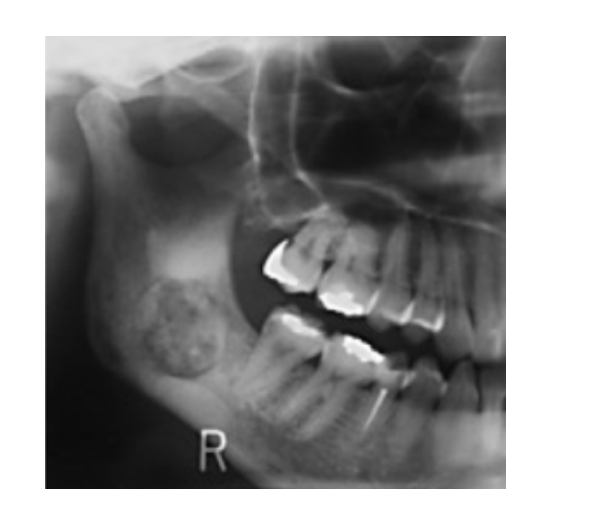

Aneurysmal Bone Cyst

Pseudocyst w/ blood-filled spaces

Posterior Mandible

* Multilocular Radiolucency:

* Expansile

Tx: Fine Needle Aspiration 1st (Blood=Confirms Dx)

* Excision